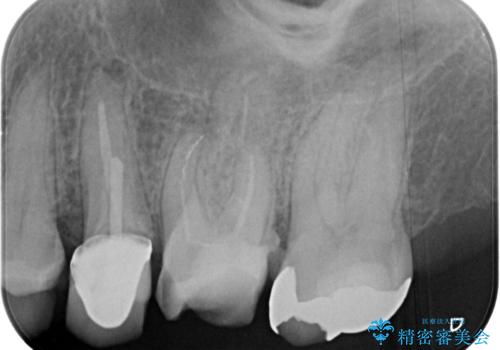

【破折ファイル除去】他院で折れた根管治療の器具をとってほしい

- 他院で折れた根管治療の器具をとってほしいという主訴で来院されました。

マイクロスコープで根管内を観察すると、除去できる状態だったため破折ファイル除去を行いオールセラミッククラウンにて修復治療しております。

通常、根尖湾曲の先にあるファイルは無理に取るより外科治療によりアプローチすることを推奨しています。